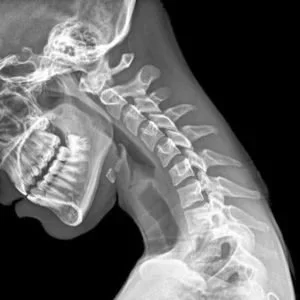

Good posture supports spinal health and optimal nervous system function

Your spine protects your spinal cord, which is the main communication pathway between your brain and body. Every movement, sensation, and internal process relies on this connection. When posture places ongoing stress on the spine, it can interfere with how efficiently your body communicates and adapts.

Your nervous system controls and coordinates everything your body does. When your spine isn’t moving well or is under stress, it can affect how signals travel between your brain and body.